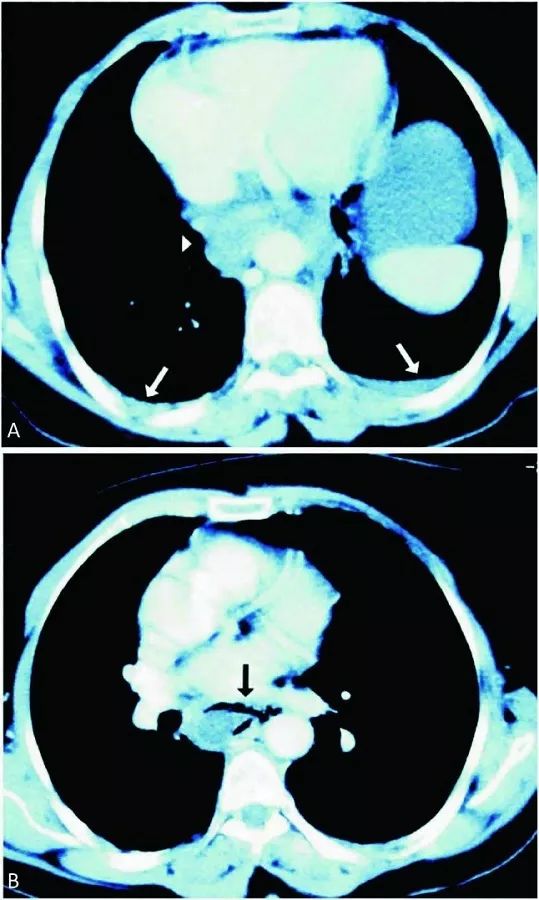

心电图提示:窦性心律,非特异性ST段改变。心肌酶、TnI水平均为正常,D-二聚体升高(13.60 ug/mL),其他实验室检查未见明显异常。急诊医生考虑胸痛原因不太可能是ACS,进行了胸片(图1)及CT检查(图2)。

图2 CT检查提示A型主动脉夹层(A, B)远端靠近右侧肾动脉主干

没有冠脉介入治疗的指征,立即联系胸外科进行紧急手术。术后患者出现房颤,连续泵入胺碘酮治疗后得以控制。术后18天患者出院,恢复良好。